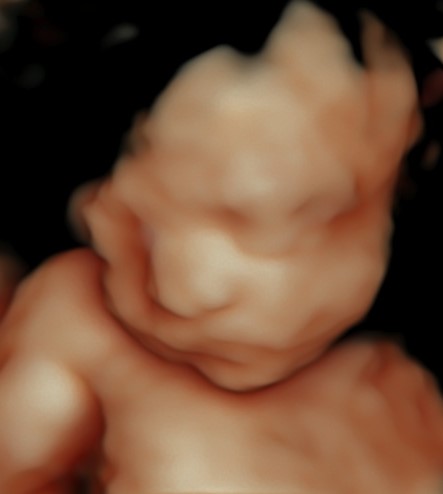

Monmouth County’s First 4D/5D/HD Live Ultrasound Studio

4D/5D/HD Ultrasound Gallery

Gallery